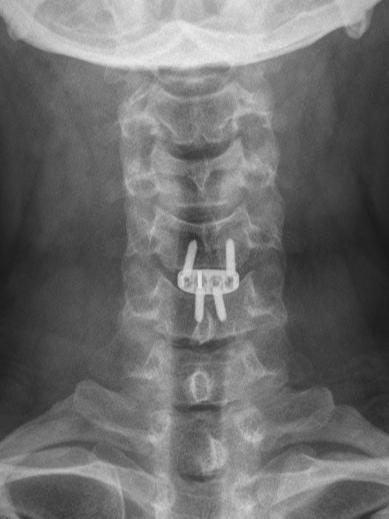

对于已确诊的脊髓型颈椎病患者,只要没有手术禁忌证,原则上应首选手术治疗。不过,对于受压较轻、病程较短、症状不重患者,也可以选择保守治疗,如卧床休息,减少颈椎负荷,佩戴颈托、颈围等支具等,但切记不要粗暴按摩。

六、颈椎手术安全吗?

对于颈椎手术,很多人会望而却步,误认为颈部大血管、神经太多,手术风险非常大,因此把病情一拖再拖。但事实上,无论是颈椎前路手术还是后路手术都是很成熟的手术,只要选择一个有经验的医生手术,风险都是可控的。

脊髓型颈椎病是一种发病隐匿、致残率高的颈椎病,需要引起我们足够重视。一旦确诊,原则上应该考虑尽早手术。不要耽误病情,错失手术良机。